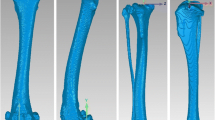

Prior to surgery, computed tomographic scansFootnote 2 with a 512 × 512 image matrix, a 0.35 × 0.35 pixel dim, and 0.5 mm slice thickness with 0.3 mm overlap were obtained over the full length of the femora, including the patellas. Three-dimensional digital bone models of the affected and contralateral femurs and patellas were created; the cortical bone margins were segmented using an open source 3D segmentation software programFootnote 3, and these point-clouds were converted into polygonal surface models with a reverse engineering software programFootnote 4. Anatomic coordinate systems were applied to the bone models based on anatomical landmarks of the patella and femur [23]. Femoral coordinates were applied such that the mediolateral axis (z-axis) passed through the center of the lateral and medial femoral condyles with the femoral origin located at the mid-point between the condyles (Fig. 1). The proximodistal axis (y-axis) passed proximally along the femoral shaft, perpendicular to the mediolateral axis in the plane common to the center of both femoral condyles and the femoral head. Patellar coordinates were applied such that the mediolateral axis (z-axis) passed through the most medial and lateral points of the bone with the patellar origin located at the mid-point between these points. The proximodistal axis (y-axis) passed proximally, perpendicular to the mediolateral axis, passing through the most proximal aspect of the patella. The craniocaudal axes (x-axis) for the femur and patella were created from the cross product of the mediolateral and proximodistal axes, thus creating Cartesian coordinate systems in each bone.